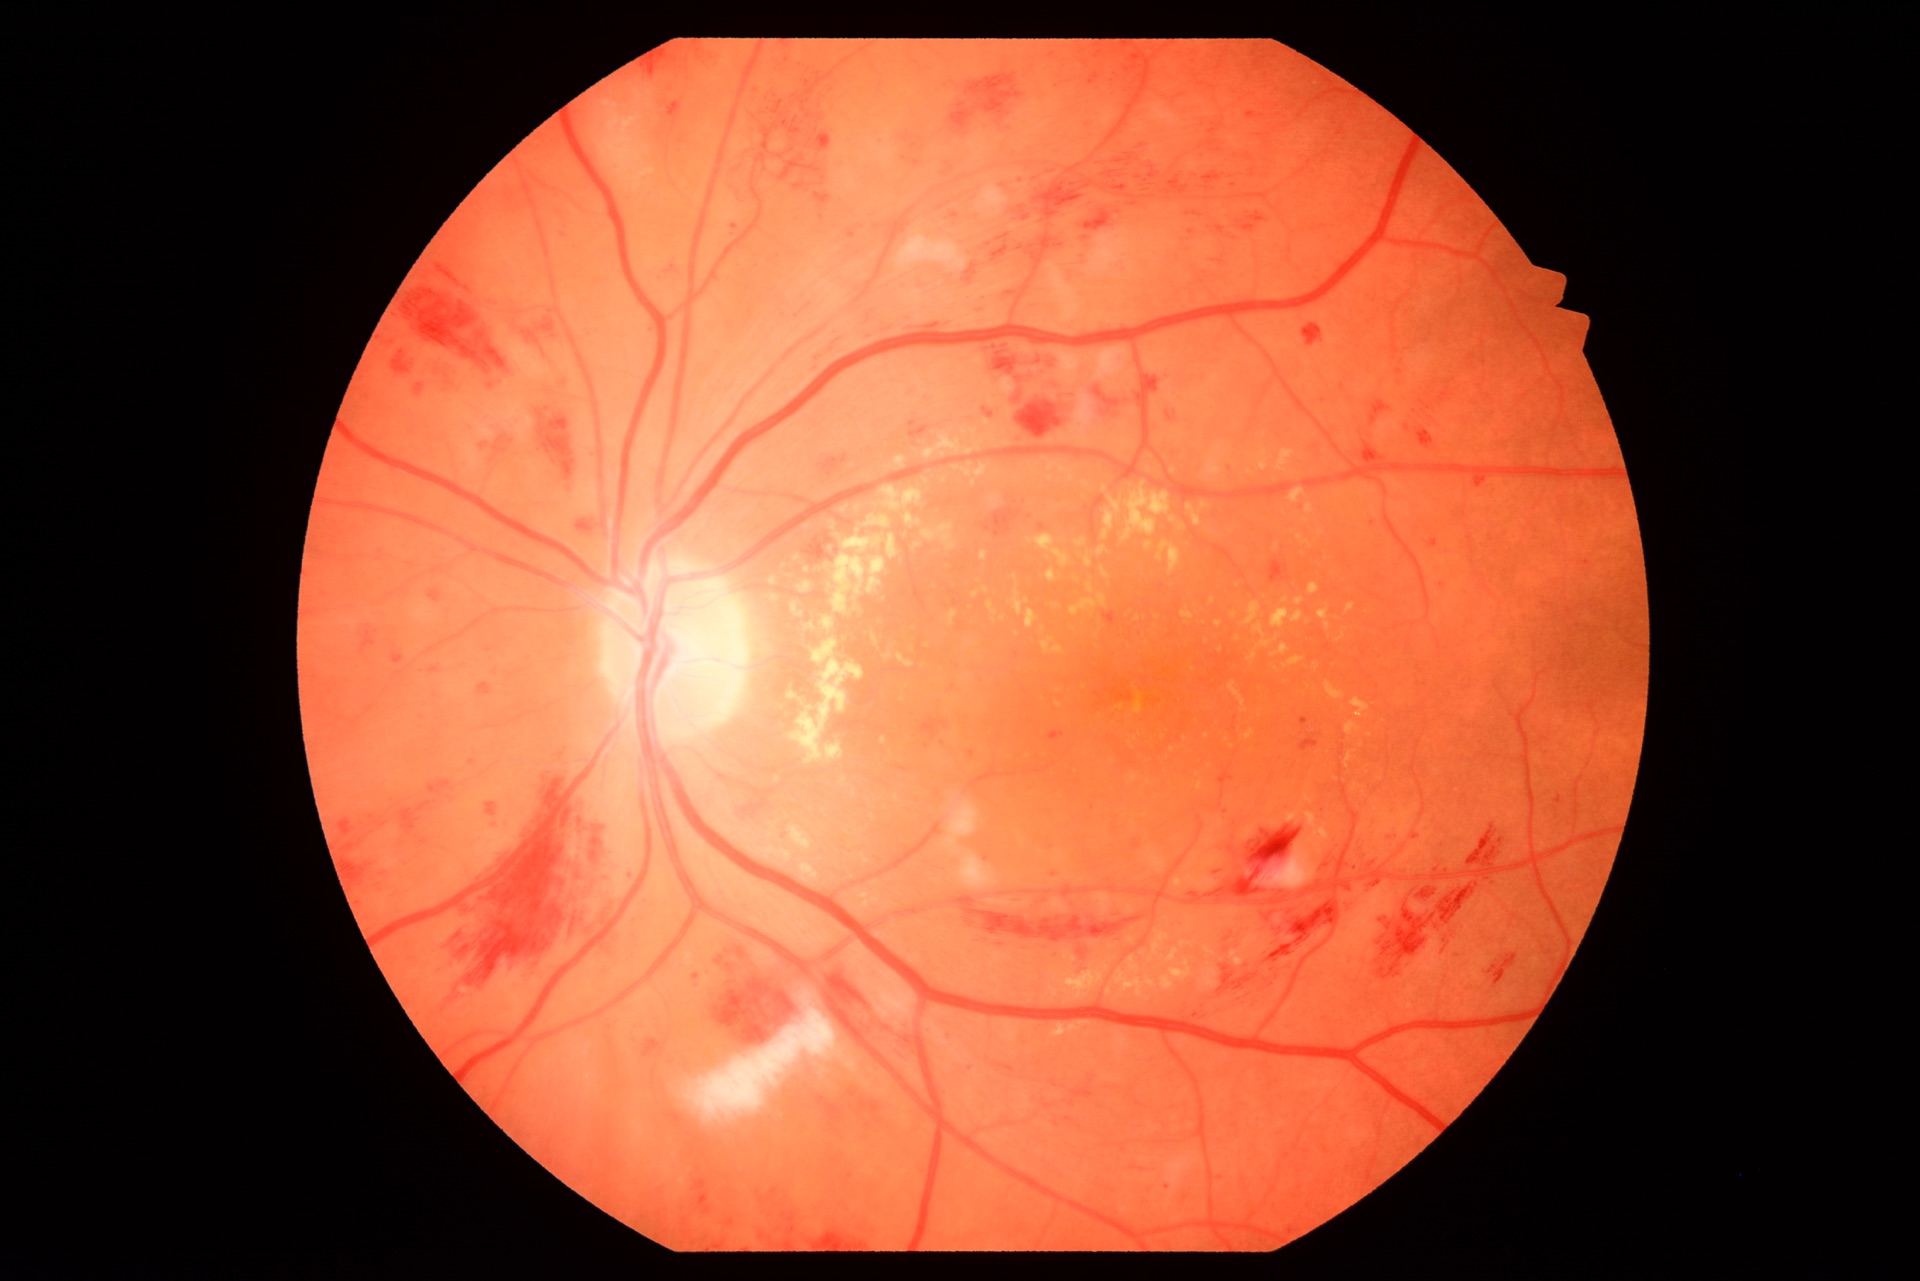

Retinal images of outstanding quality

The VX-20 enables non-mydriatic imaging at 45° and 27° angles, as well as mydriatic and FA imaging at 50° and 30° angles. In addition, the VX-20 features an autofluorescence mode for further diagnostic examinations of the retina, such as AMD testing. In combination with the VK-2 software, the VX-20 offers extraordinary possibilities for the analysis of fundus images.